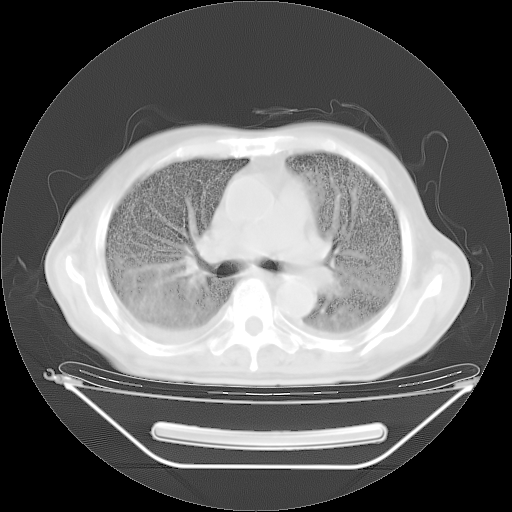

今天复查肺部CT,发现双肺广泛磨玻璃样改变。所以我把3月19日和5月9日相隔50天的肺部CT上传。请大家会诊。

2009年3月19日肺部CT片。

2009年3月19日肺部CT